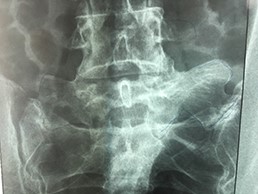

A 42-year-old female presented to the clinic with a history of chronic low back pain. She reported no relevant medical history. She had already been treated in the last 4 years by general practitioners with analgesics and home based physiotherapy with no satisfactory results. She had two previous admissions to the emergency department where morphine was prescribed to control the pain on her lower back. She was under ambulatory treatment with diclofenac, and tizanidine with partial relief of symptoms. Her main complaint was pain on the lower lumbar back with no radiation to the lower extremities. In her physical evaluation she presented limitation to full rotation and bending of the lumbar spine due to pain. Lasegue sign was negative, sensitivity, reflexes, sagittal balance, distal muscular strength and pulses were normal. Radiographs showed an overdeveloped left transverse process of the fifth lumbar vertebra which contacts with the sacrum at the left sacral wing with signs of degeneration at the same site (Fig. 1). Magnetic resonance imaging (MRI) studies were obtained (Figs 2–5). The patient was taken to the operating room where infiltration with 1 mL of lidocaine and 40 mg of Triamcinolone was performed in the pseudoarticulation between the left transverse process and the sacrum under fluoroscopic guidance. She reported a complete relief of pain after the procedure. At three months follow-up she was managed with strengthening and stabilizing exercises for the lumbar spine and postural education was initiated. She remains asymptomatic at her 12 months follow up.

Radiographs showing an overdeveloped left transverse process, which contacts with the sacrum left sacral wing (Castelvi’s Type IIa).